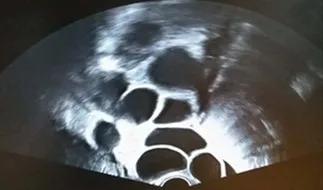

本以为多年的顽疾被治愈了,直到2017年,小丽再次出现了月经淋漓不净。经朋友介绍,小丽来到了郑大三附院生殖医学中心,找到了主任医师管一春。管一春仔细询问了她的病史后,随即让患者做了超声检查,果不其然,双侧卵巢多发囊肿。

明确了病因,小丽立即进行了垂体伽马刀治疗。但是3个月后,垂体瘤再次复发。考虑到她的卵巢体积较大,为了避免卵巢扭转、囊肿破裂等风险,同时根据激素水平判断,这多发的卵巢囊肿可能是多卵泡发育,管一春建议对其进行尝试性取卵。可喜的是,小丽最终获卵14枚,行体外受精,形成了4枚可利用胚胎。